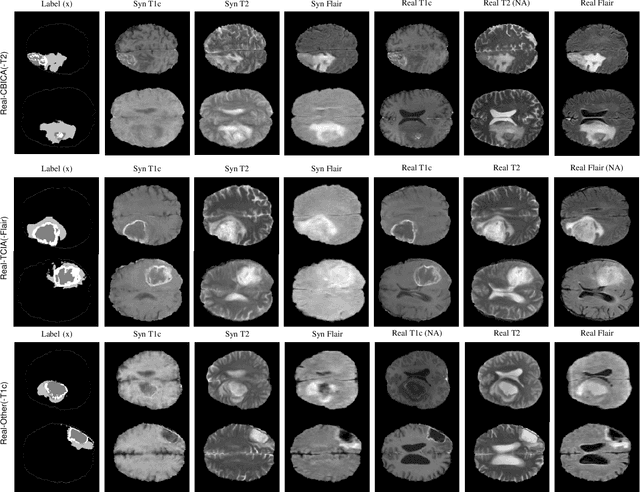

Abstract:Multi-modality images have been widely used and provide comprehensive information for medical image analysis. However, acquiring all modalities among all institutes is costly and often impossible in clinical settings. To leverage more comprehensive multi-modality information, we propose a privacy secured decentralized multi-modality adaptive learning architecture named ModalityBank. Our method could learn a set of effective domain-specific modulation parameters plugged into a common domain-agnostic network. We demonstrate by switching different sets of configurations, the generator could output high-quality images for a specific modality. Our method could also complete the missing modalities across all data centers, thus could be used for modality completion purposes. The downstream task trained from the synthesized multi-modality samples could achieve higher performance than learning from one real data center and achieve close-to-real performance compare with all real images.